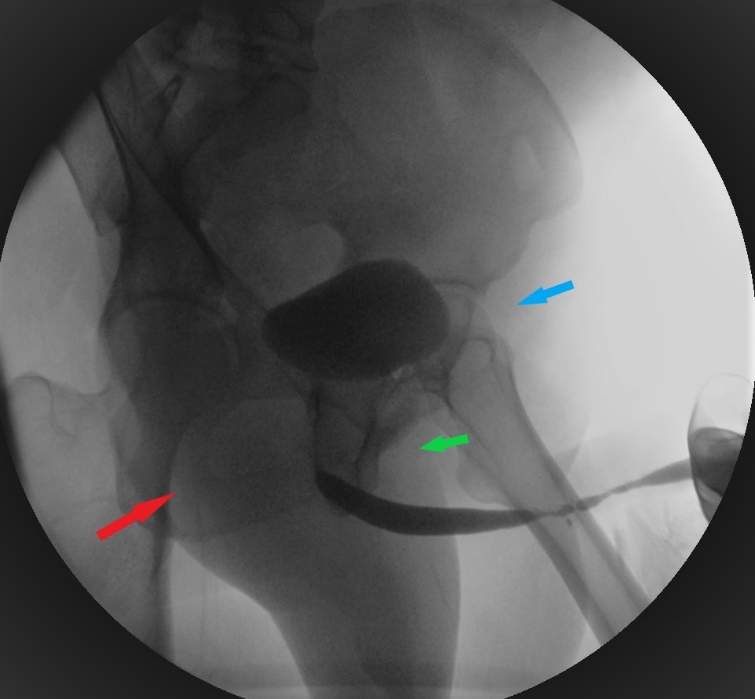

- La uretrocistografía retrógrada/miccional (UCG), es un examen dinámico que se realiza mediante la instilación uretral de contraste hidrosoluble bajo fluoroscopía y se recomienda que siempre sea hecha por el urólogo entrenado.20 Es el examen de elección para etapificación de las E/E. La UCG se encarga de definir la longitud, ubicación, severidad y número de las E/E. Además, da información sobre fístulas, duplicación uretral, falsa vía y el status del cuello vesical. El estudio completo consta de 2 fases: la fase retrógrada dibuja la uretra anterior y la fase miccional dibuja la uretra posterior, no siendo intercambiables, como se muestra en las imágenes.

La fase retrógrada debe realizarse con el paciente en decúbito lateral con inclinación de 45°, permitiendo ver un orificio obturador “ocluido” en la imagen; con la cadera inferior flectada igualmente en 45° y la cadera superior extendida, y con el pene en estiramiento. (Figura 5).